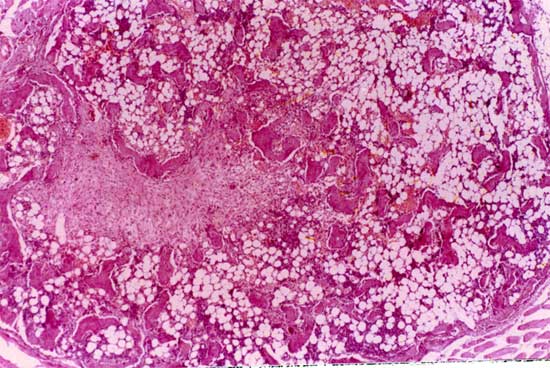

植骨材料以自体骨疗效为最佳。迄今仍被视为“金标准”,但取骨会增加病人痛苦,且供骨量有限,特别是儿童。 同种异体骨移植有传播人类疾病的危险,有一定的免疫原性,来源也受限。 植骨术见诸报道已有300余年。1688年荷兰医生Job Meekeren记述了第一例异种骨移植手术。他用狗颅骨修复一位士兵的颅骨缺损,因这种疗法违反基督教教义,病人被逐出教会。 异种骨取之于动物,来源丰富,易于大量获取和加工贮存,用作植骨材料有巨大开发潜力,但未经处理的异种骨植入体内可引起强烈的免疫排斥反应,采用多种理化方法处理,在消除其抗原性的同时也使有益的生物活性物质破坏殆尽,这就是异种骨长期不能应用于临床的原因。 如果将成骨活性物质浓集,与经过处理的异种骨松质骨复合,后者是良好的缓释载体,具有高效诱导成骨能力,且移植骨之尺寸和生物学活性可根据缺损大小及个体需要而制作成合适的“预制件”。这是将BMP与适当载体结合的一种新方式,为更好地利用异种骨开辟了一条新途径。 为了进一步提高BMP及其复合材料应用于骨折愈合与骨缺损修复能力,我们将复合BMP的异种骨与自体成骨细胞共同培养,使细胞长入骨孔内,再将骨块植入体内,获得良好成骨效果。

复合BMP的异种骨与自体成骨细胞共同培养, 使细胞长入骨孔内,再将骨块植入体内,获得良好成骨效果